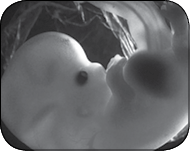

Начинается развитие тонкого кишечника и надпочечников. Происходит закладка почек и мочевого пузыря. Начинает работать печень (она вырабатывает красные кровяные клетки). Формируется лицо. Крошечные конечности удлиняются. Глазки частично прикрыты веками. Между головкой и тельцем образуется сужение – будущая шея. А между ножками выступает бугорок, из которого разовьются наружные половые органы. Длина тельца – 7 мм, масса тела будущего малыша – около 1 грамма.